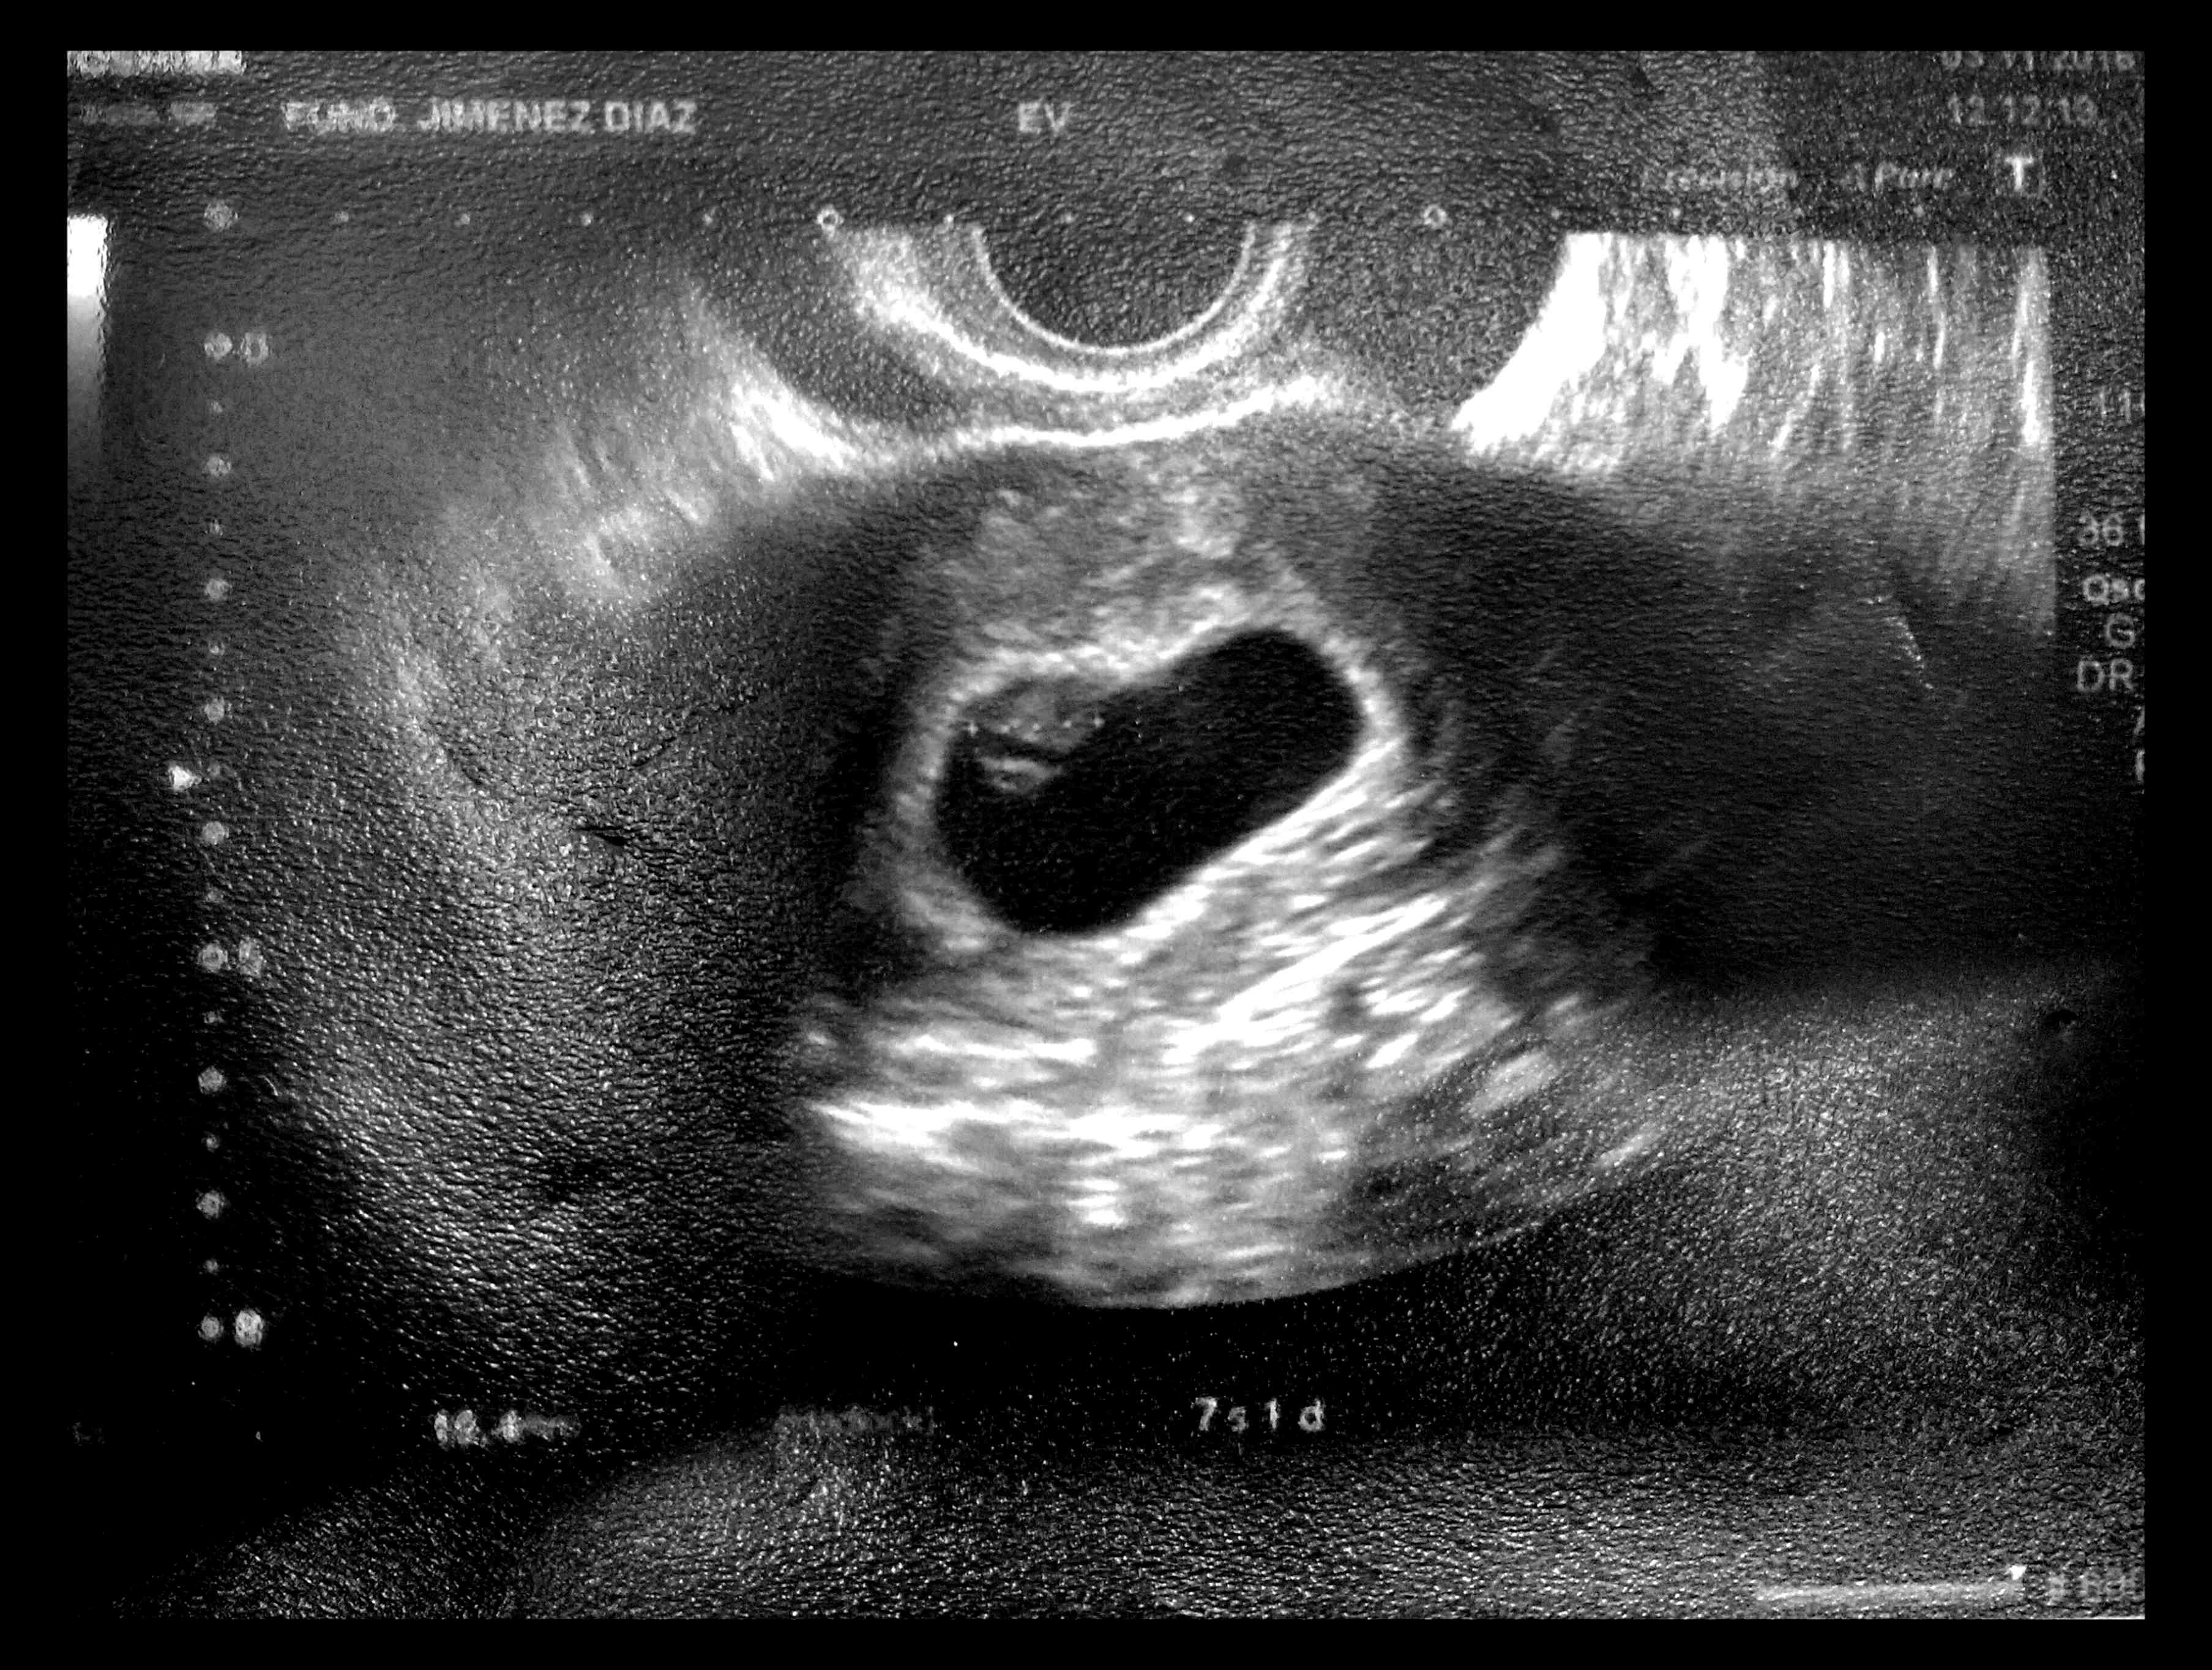

El 12 de Octubre a las 8 de la mañana tuvimos la primera confirmación: habemus alien.

A los pocos días llegó el primer avistamiento. Poco antes de los dos meses, segundo impacto visual.

Así que ahí está nuestro bebé de Schrödinger (no sabemos si es él o ella o ello o qué).